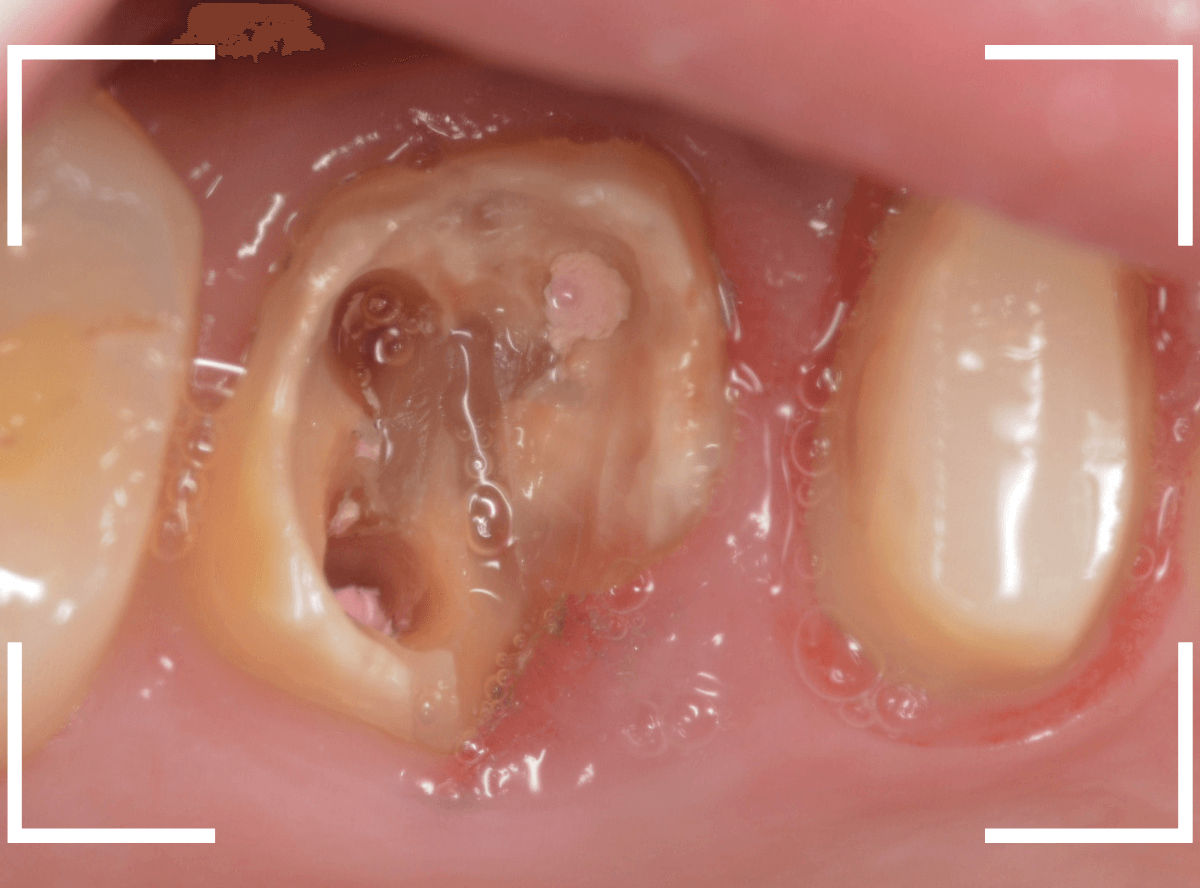

レントゲン写真では問題なさそうでしたが、メタルコアを除去すると、中は真っ黒でした。

このように、コアの中で虫歯が進行している場合もありますので、さし歯をやり直す際は、出来る限りコアも外して調べるようにしています。

虫歯を全て除去しました。

幸い、あまり多く削る事なく進められたので良かったです。